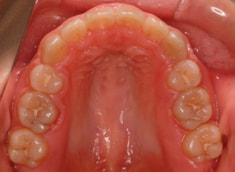

治療前